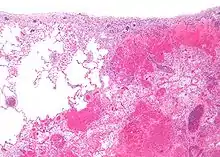

Micrograph of a pulmonary infarct (right of image) beside relatively normal lung (left of image). H&E stain.

Infarction is tissue death (necrosis) due to inadequate blood supply to the affected area. It may be caused by artery blockages, rupture, mechanical compression, or vasoconstriction.[1] The resulting lesion is referred to as an infarct[2][3] (from the Latin infarctus, "stuffed into").[4]